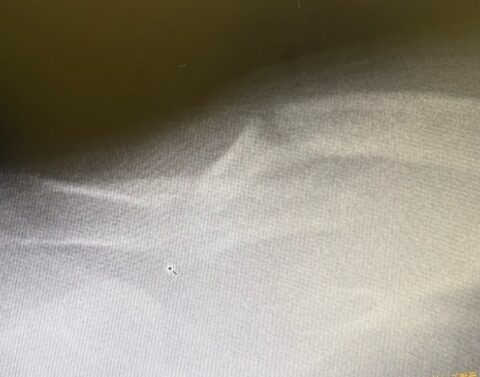

因みに、骨折した骨はお互い接着剤を出してくっつき合うようになるそうです。毎回レントゲンにより、骨の接着が順調か否かを見させてもらいました。くっきりした骨が段々ぼやけてくる状態が接着している状態のようです。そして骨が太くなっていくのですが、ある程度まで進むと余分な骨は消えてスムーズな状態になっていくそうです。また、動きによっては痛みを感じるときに、骨は「もっと強くならねば」となるようで、痛いからと言って過保護になるよりも、どんどん痛みを感じるようにすることで骨に気づきを与える必要があるようです。

段々とぼけている状態が骨が接着剤を出して、くっつき始めているらしいです